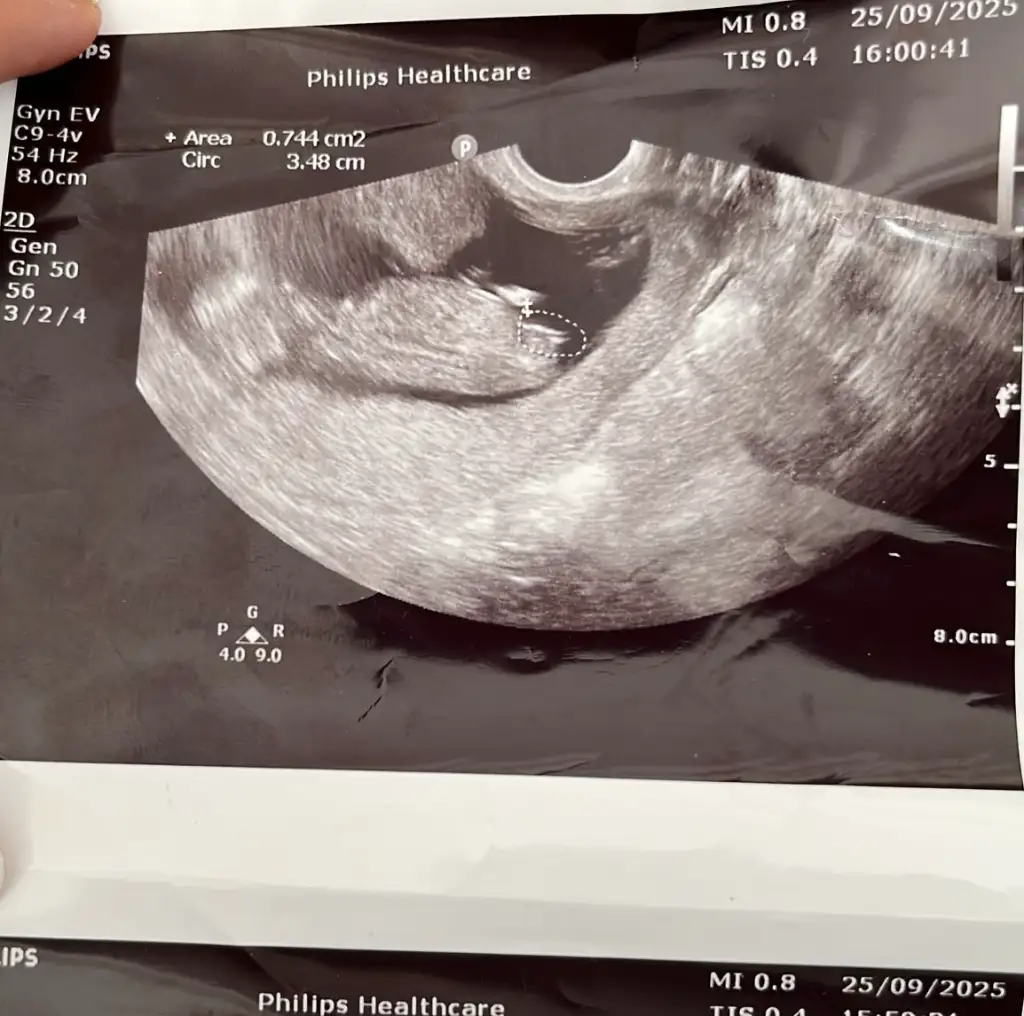

Kaçıncı haftada kız demişlerdi kuzum benim son gittiğim 12+ 4 te doktor da buna göre kız dedi ama bacak arası falan görmedi nuba göre yorum yaptı anlıyorsan bir bakar mısınBenimde nub kız görünüyordu canım erken dönemde zaten kız olarak görünüyor tüm bebekler eğer biraz daha değişmezse kızdır erkek erken gösteriyor genelde

eski fotolara baktım canım gördüm bebişini ama 1 fotoğraf haricinde diğerlerinin nubu erkek gibi bir de 11+…. değişmeler olabiliyor haklsın ama benimkiler 12+ 2 diğer 12+4Benimde nub kız görünüyordu canım erken dönemde zaten kız olarak görünüyor tüm bebekler eğer biraz daha değişmezse kızdır erkek erken gösteriyor genelde

Anladım canım evet kız ama kız denilip nubu kız olup sonradan dikleşen var mı diye merak ettim doktor da kız dedi kesin olmamakla beraberYok doktor en başından beri erkek dedi 13. Haftada öğrendim ama chat gpt kız diyordu yani doğru tahminde bulunmuyor onu söylemek istedim. Sizin bebiş bana kız gibi geldi ama

Daha haftası da küçükmüş değişebilir evet bende ilk söylediklerinde tamam kesin erkektir diyemedim küçük olduğu için en doğru sonuç 16. Haftadan sonra olurAnladım canım evet kız ama kız denilip nubu kız olup sonradan dikleşen var mı diye merak ettim doktor da kız dedi kesin olmamakla beraber

İnşallah doktor da kesin demedi ama ben güveniyorum 12+4 nub için yeterli bir zaman bir de benimki sanki çok bariz hayırlısı olsun belki dikleşir rabbimin elinde herşeyDaha haftası da küçükmüş değişebilir evet bende ilk söylediklerinde tamam kesin erkektir diyemedim küçük olduğu için en doğru sonuç 16. Haftadan sonra olur